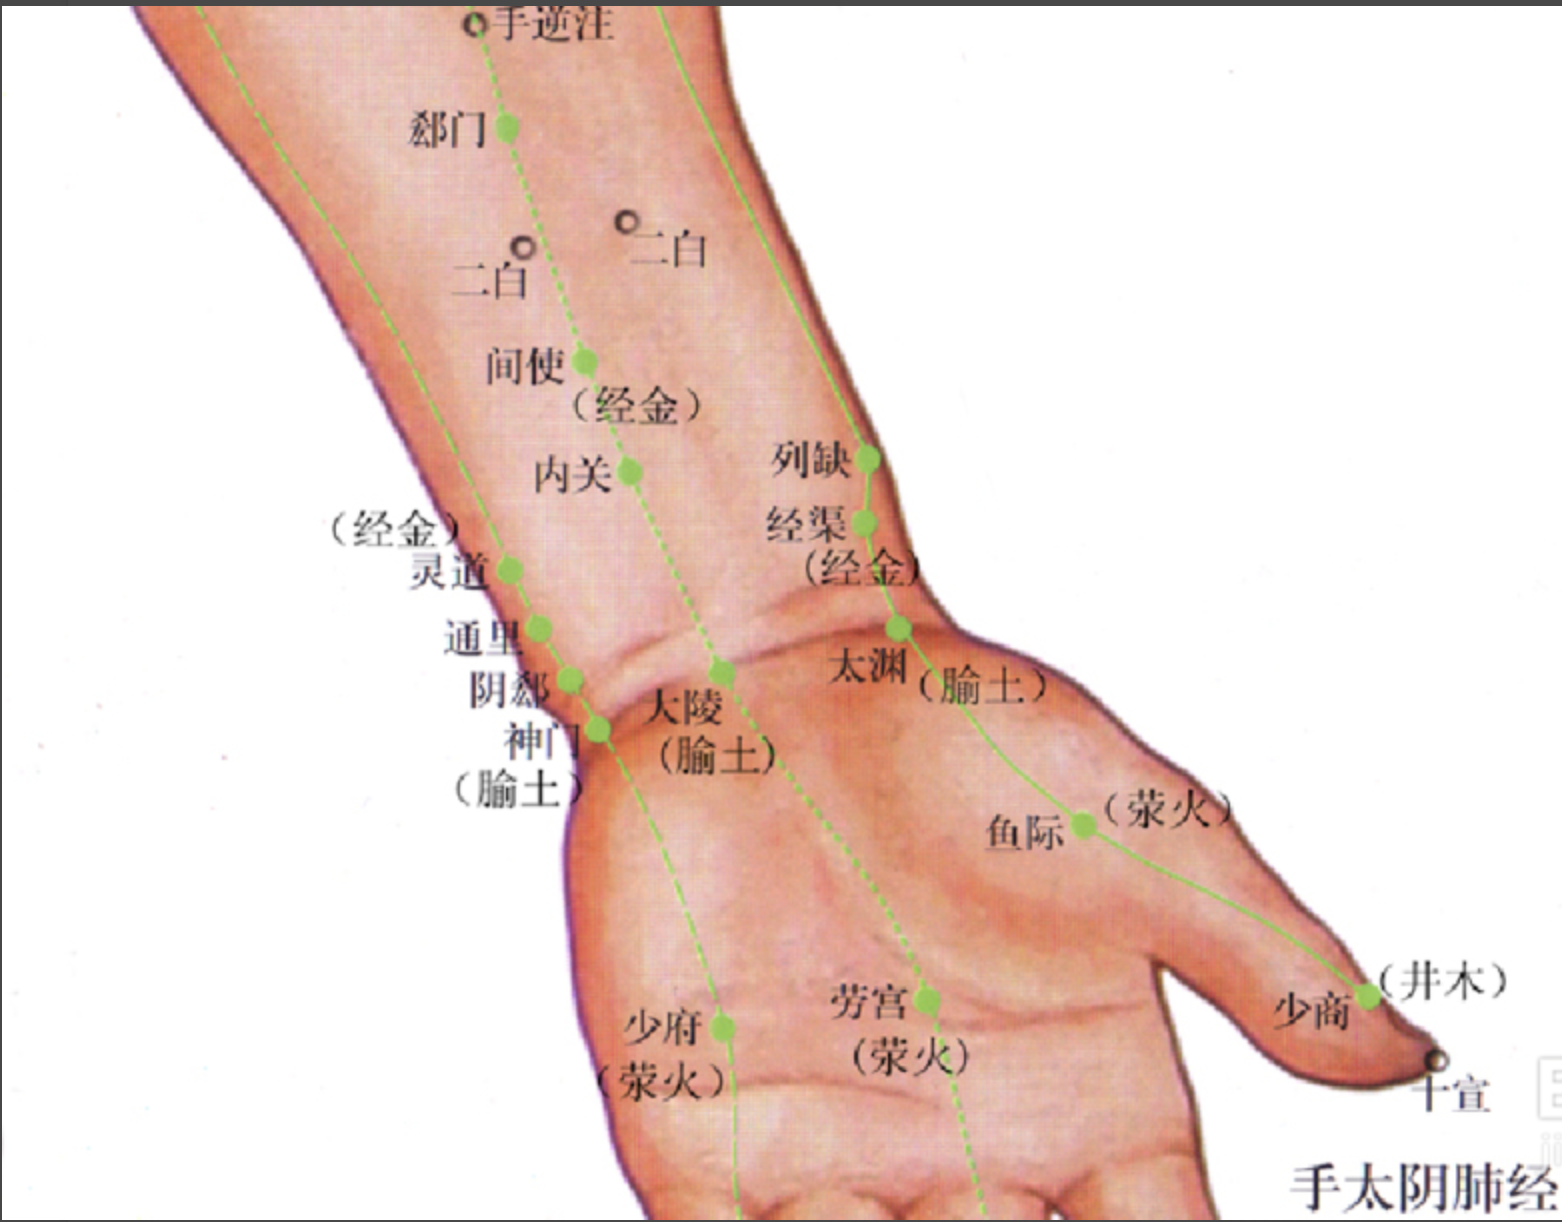

【(一)手太阴肺经(图10-19-1)】

图 10-19-1 手太阴肺经循行及常用腧穴

1、时辰 寅时 3 ~ 5

2、歌诀 手太阴肺十一穴,中府云门天府列,次则侠白下尺泽,又次孔最与列缺,经渠太渊下鱼际,抵指少商如韭叶。

3、经脉循行 肺手太阴之脉,起于中焦,下络大肠,还循胃口,上膈属肺,从肺系横出腋下,下循臑(nào)内,行少阴心主之前,下肘中,循臂内上骨下廉,入寸口,上鱼,循鱼际,出大指之端;其支者,从腕后直出次指内廉,出其端。

即该经起自中焦,向下联络大肠,回过来沿着胃的上口贯穿膈肌,入属肺脏,从肺系(气管、喉咙)横行出胸壁外上方(中府),走向腋下,沿上臂前外侧,行于手少阴心经和手厥阴心包经的外面,至肘中(尺泽)后再沿前臂桡侧下行至寸口(桡动脉搏动处),又沿大鱼际外缘出拇指桡侧端(少商)。

其支脉从腕后桡骨茎突上方(列缺)分出,经手背虎口部至食指桡侧端(商阳)。脉气由此与手阳明大肠经相接。

4、主要证候 咳嗽气喘气短、咳血咽痛,外感伤风,循行部位痛麻或活动受限等。

5、主治概要 主治外感、头痛、项强、咳痰喘等证。

尺泽

【定位】 在肘横纹中,肱二头肌腱桡侧凹陷处(图 10-19-2)。

【主治】 咳嗽,气喘,咳血,潮热,胸部胀满,咽喉肿痛,小儿惊风,吐泻,肘臂挛痛。

【配伍】 配太渊、经渠治咳嗽、气喘,配孔最治咳血、潮热,配曲池治肘臂挛痛。

【刺灸法】 直刺 0.8 ~ 1.2 寸,或点刺出血。

【附注】 手太阴经所入为“合”。

列缺

【定位】 在前臂桡侧缘,桡骨茎突上方,腕横纹上 1.5 寸,当肱桡肌与拇长展肌腱之间。

简便取穴:两手虎口自然平直交叉,一手食指按在另一手桡骨茎突上,指尖下凹陷中是穴。

【主治】 伤风,头痛,项强,咳嗽,气喘,咽喉肿痛,口眼歪斜,齿痛。

【配伍】 配合谷治伤风头痛,项强,配肺俞治咳嗽,气喘。

【刺灸法】 向上或向下斜刺 0.5 ~ 0.8 寸。

【附注】 手太阴经络穴;八脉交会穴之一,通于任脉。

太渊

【定位】 在腕掌侧横纹桡侧,桡动脉的桡侧凹陷中。

【主治】 咳嗽,气喘,咳血,胸痛,咽喉肿痛,腕臂痛,无脉症。

【配伍】 配尺泽、鱼际、肺俞治咳嗽、咳血、胸痛,配人迎治无脉症。

【刺灸法】 避开桡动脉,直刺 0.3 ~ 0.5 寸。

【附注】 手太阴经所注为“输”;肺经原穴;脉会太渊。

少商

【定位】 在手拇指末节桡侧,距指甲角 0.1 寸。

【主治】 咽喉肿痛,咳嗽,鼻衄,发热,昏迷,癫狂。

【配伍】 三棱针点刺出血,配合谷治咽喉肿痛,配中冲治昏迷、发热。

【刺灸法】 浅刺 0.1 寸,或点刺出血。

【附注】 手太阴经所出为“井”。